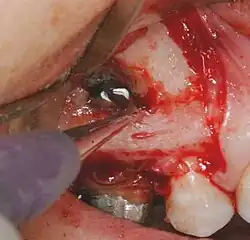

Chirurgie explorative

L'objectif d'une chirurgie explorative est de diagnostiquer un problème endodontique qui ne peut être diagnostiqué autrement. Il est nécessaire de pratiquer un lambeau pour examiner la zone, en regard d'une fracture radiculaire longitudinale. On peut pratiquer le traitement approprié en même temps que cette exploration.